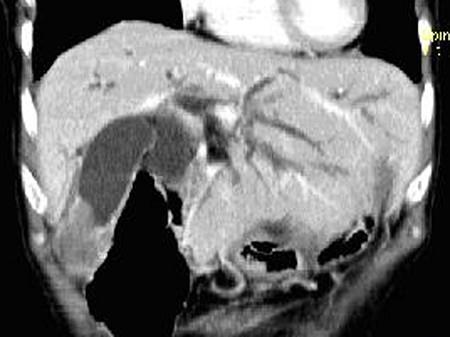

问题 患者,男,51岁,右上腹隐痛2月余,CT扫描如图,最可能的诊断是 ( )

选项 A.胆囊癌伴肝门胰头周围转移 B.胆囊息肉 C.胆囊黄色肉芽肿 D.慢性胰腺炎并胆囊息肉 E.胆囊腺瘤及慢性胰腺炎

答案 A